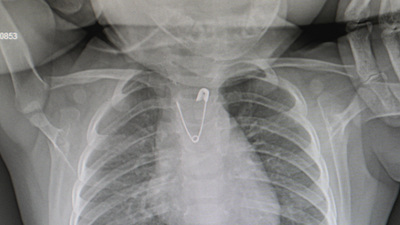

Annenin bu esnada bebeğinin yakasına takılan duanın çengelli iğnesinin olmadığını fark ettiğini ve ailenin bunun üzerine hemen acil servise başvurduğunu belirten Çalışkan, "Bebeğimizin acil serviste çekilen akciğer grafisinde açık ağızlı bir çengelli iğnenin yemek borusunun en dar yeri olan üst kısmı tıkadığını gördük. Bu da çocuğumuzun kusmasına, beslenememesine neden oluyordu. Hemen ameliyathaneye alarak anestezi altında yapılan endoskopi işlemiyle çengelli iğneyi çıkarttık" bilgisini paylaştı.

Bu durumun anlatıldığı kadar basit bir işlem olmadığını, bebeğin yuttuğu çengelli iğnenin ucunun açık olmasının cerrahi olarak çıkarılmasını da zorlaştırdığını vurgulayan Çalışkan, "Bu işlem yapılırken yemek borusunda yırtık, kanama ve ciddi hayati tehlike yaratan durumlar söz konusu olabilirdi. Ama işlemi başarıyla gerçekleştirdik, şu anda her şey yolunda, bebeğimiz beslenebiliyor" diye konuştu.